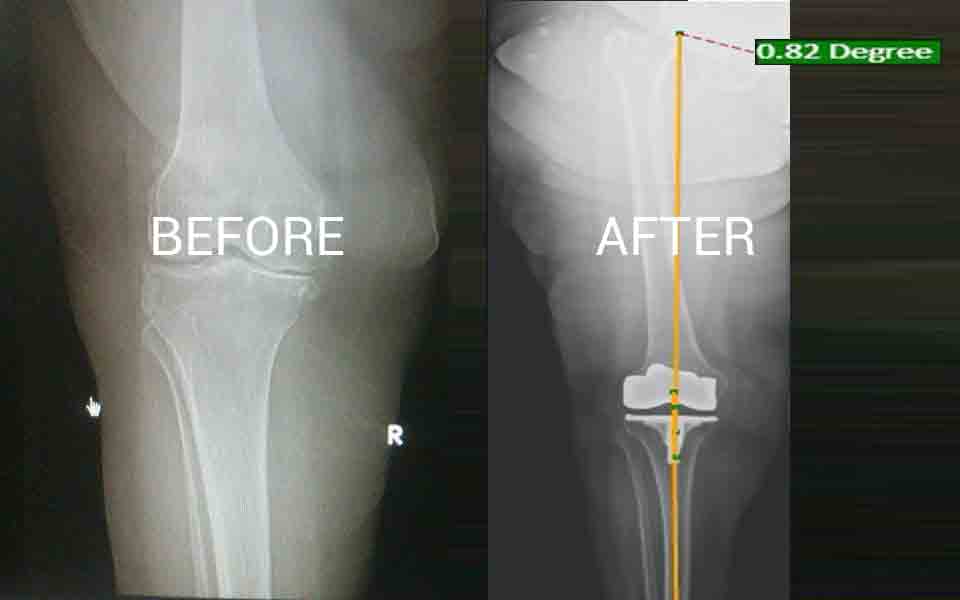

Total Knee Replacement at MHB using Augmented Reality Pixee system